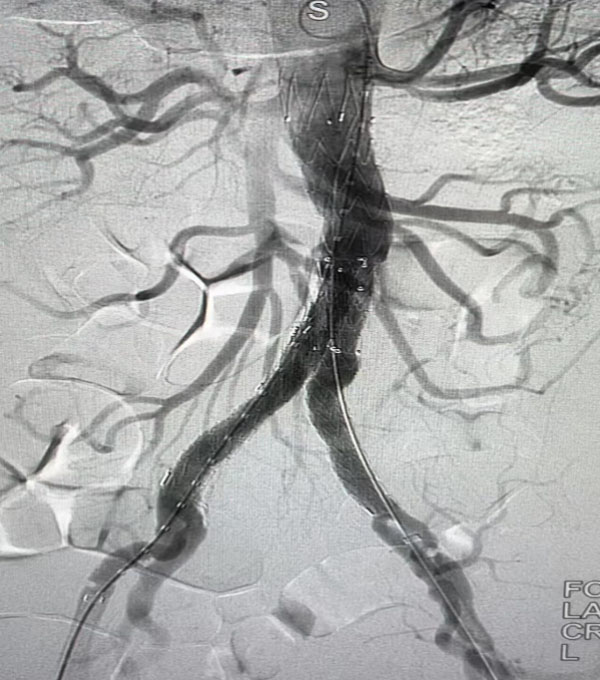

高度评价。紧接着,手术团队又为一名79岁腹主动脉瘤患者进行了腹主动脉腔内修复手术,效果良好,同样受到与会专家的好评。

腹主动脉腔内隔绝